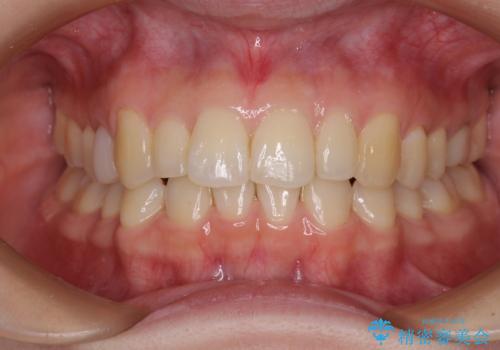

先天欠損のある歯列 インビザライン矯正

- 上顎前歯の突出感を気にして来院された患者様です。

下顎前歯2本が先天欠損しており、上顎歯列に対して、下顎歯列がアンバランスに小さい状況でした。

左右上顎側切歯2本が矮小歯であるため、上顎の抜歯ではなく、IPR(歯と歯の間を削る)と歯列全体の後方移動によってバランスを整えることとしました。

歯列のバランスが悪く、インビザライン矯正特有の奥歯の噛みにくさがなかなか改善されず、治療期間が長期化してしまいました。